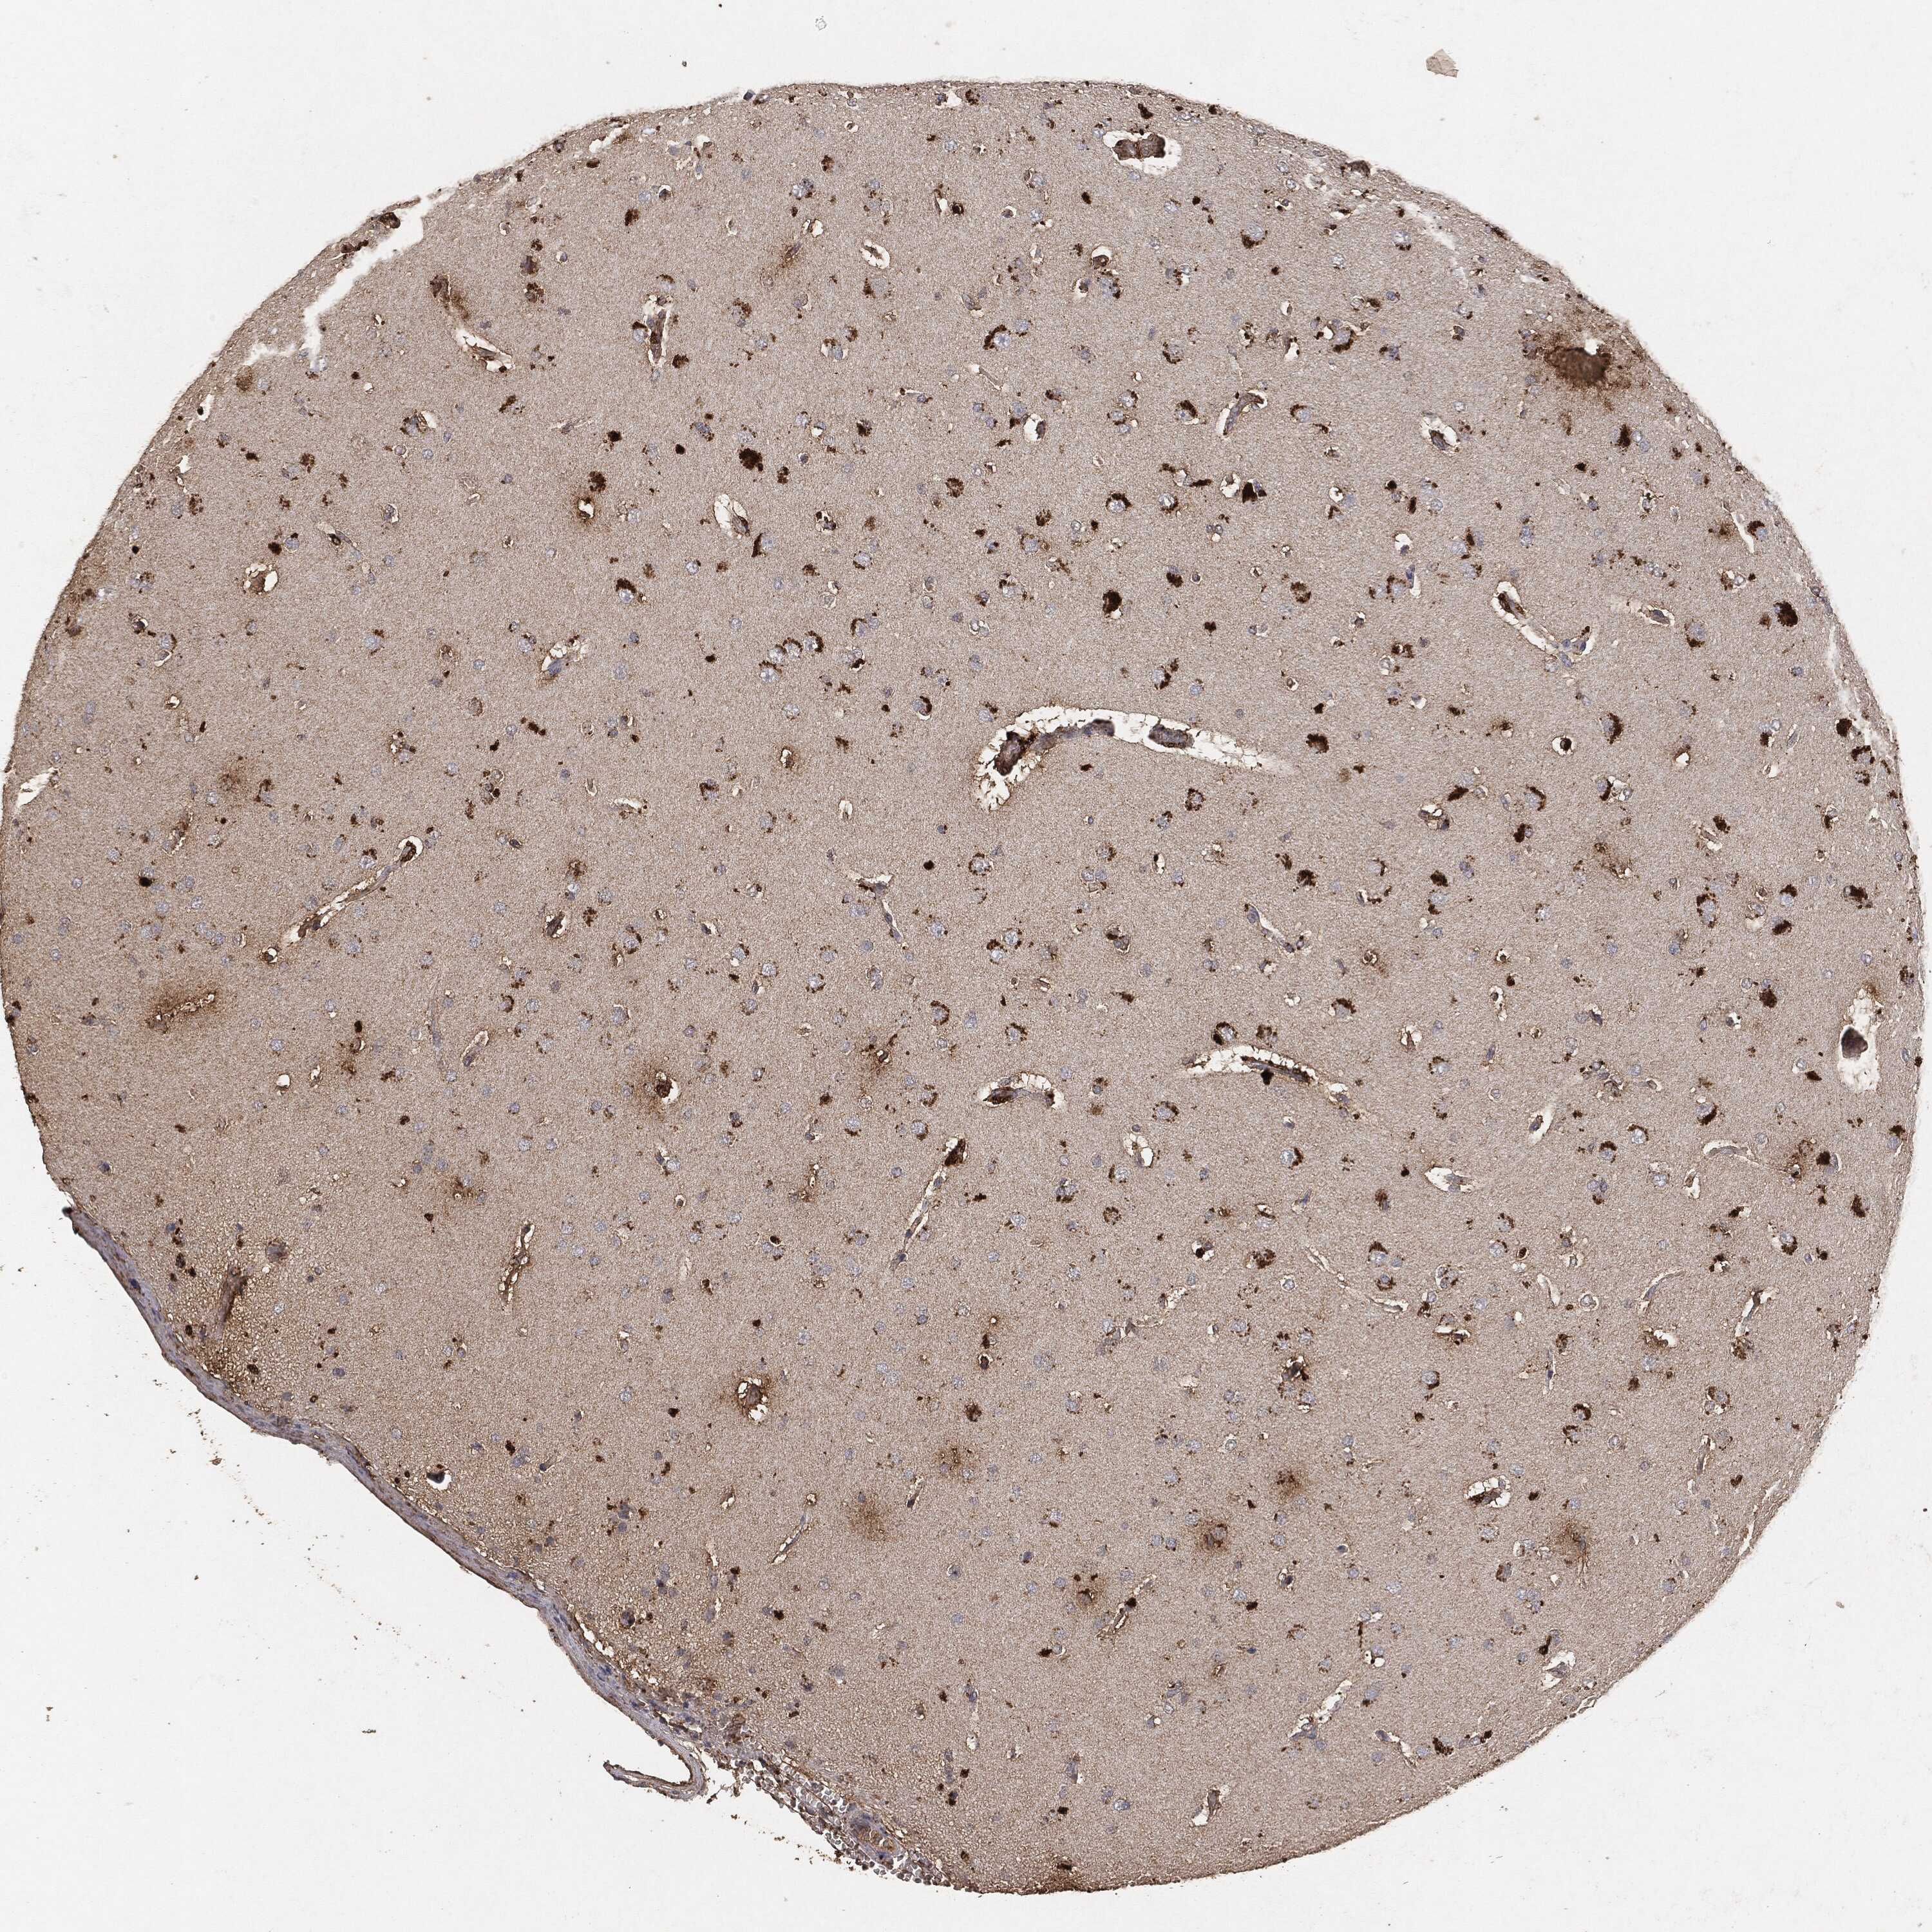

GLIOMA - Protein expressioni

A mouse-over function shows sample information and annotation data. Click on an image to view it in a full screen mode. Samples can be filtered based on level of antibody staining by selecting one or several of the following categories: high, medium, low and not detected. The assay and annotation is described here.

Note that samples used for immunohistochemistry by the Human Protein Atlas do not correspond to samples in the TCGA dataset.

Antibody stainingi

Antibody staining in the annotated cell types in the current human tissue is reported as not detected, low, medium, or high, based on conventional immunohistochemistry profiling in selected tissues. This score is based on the combination of the staining intensity and fraction of stained cells.

Each image is clickable and will lead to virtual microscopy that enables deeper exploration of all samples and also displays staining intensity scores, fraction scores and subcellular localization as well as patient and tissue information for each sample.

Glioma, malignant, High grade

Glioma, malignant, Low grade

Glioma, malignant, NOS